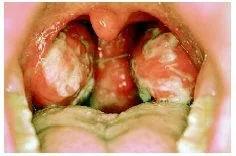

Enfeksiyöz mononükleoz

Ateş, baş ağrısı, vücudun çeşitli kesimlerinde rahatsızlıklar ve ağrılar, boyunda, belde ve koltuk altlarındaki lenf bezlerinin şişmeleri. Dalak büyür ve kalp hücrelerinde bazı değişiklikler meydana gelir.

a. Boğaz enfeksiyonu.